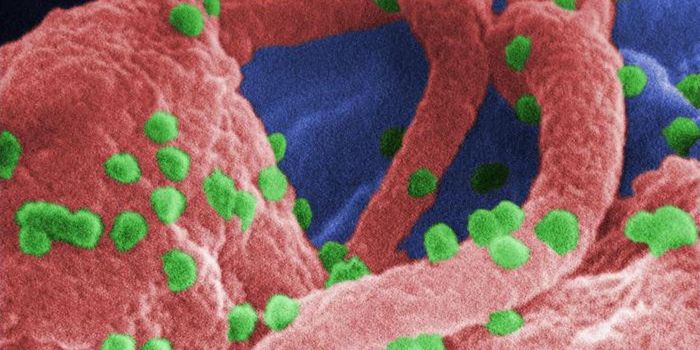

MAR 15, 2020MicrobiologyNew research has suggested that after long-term follow-up, HIV is no longer detectable in a patient that was previously ...